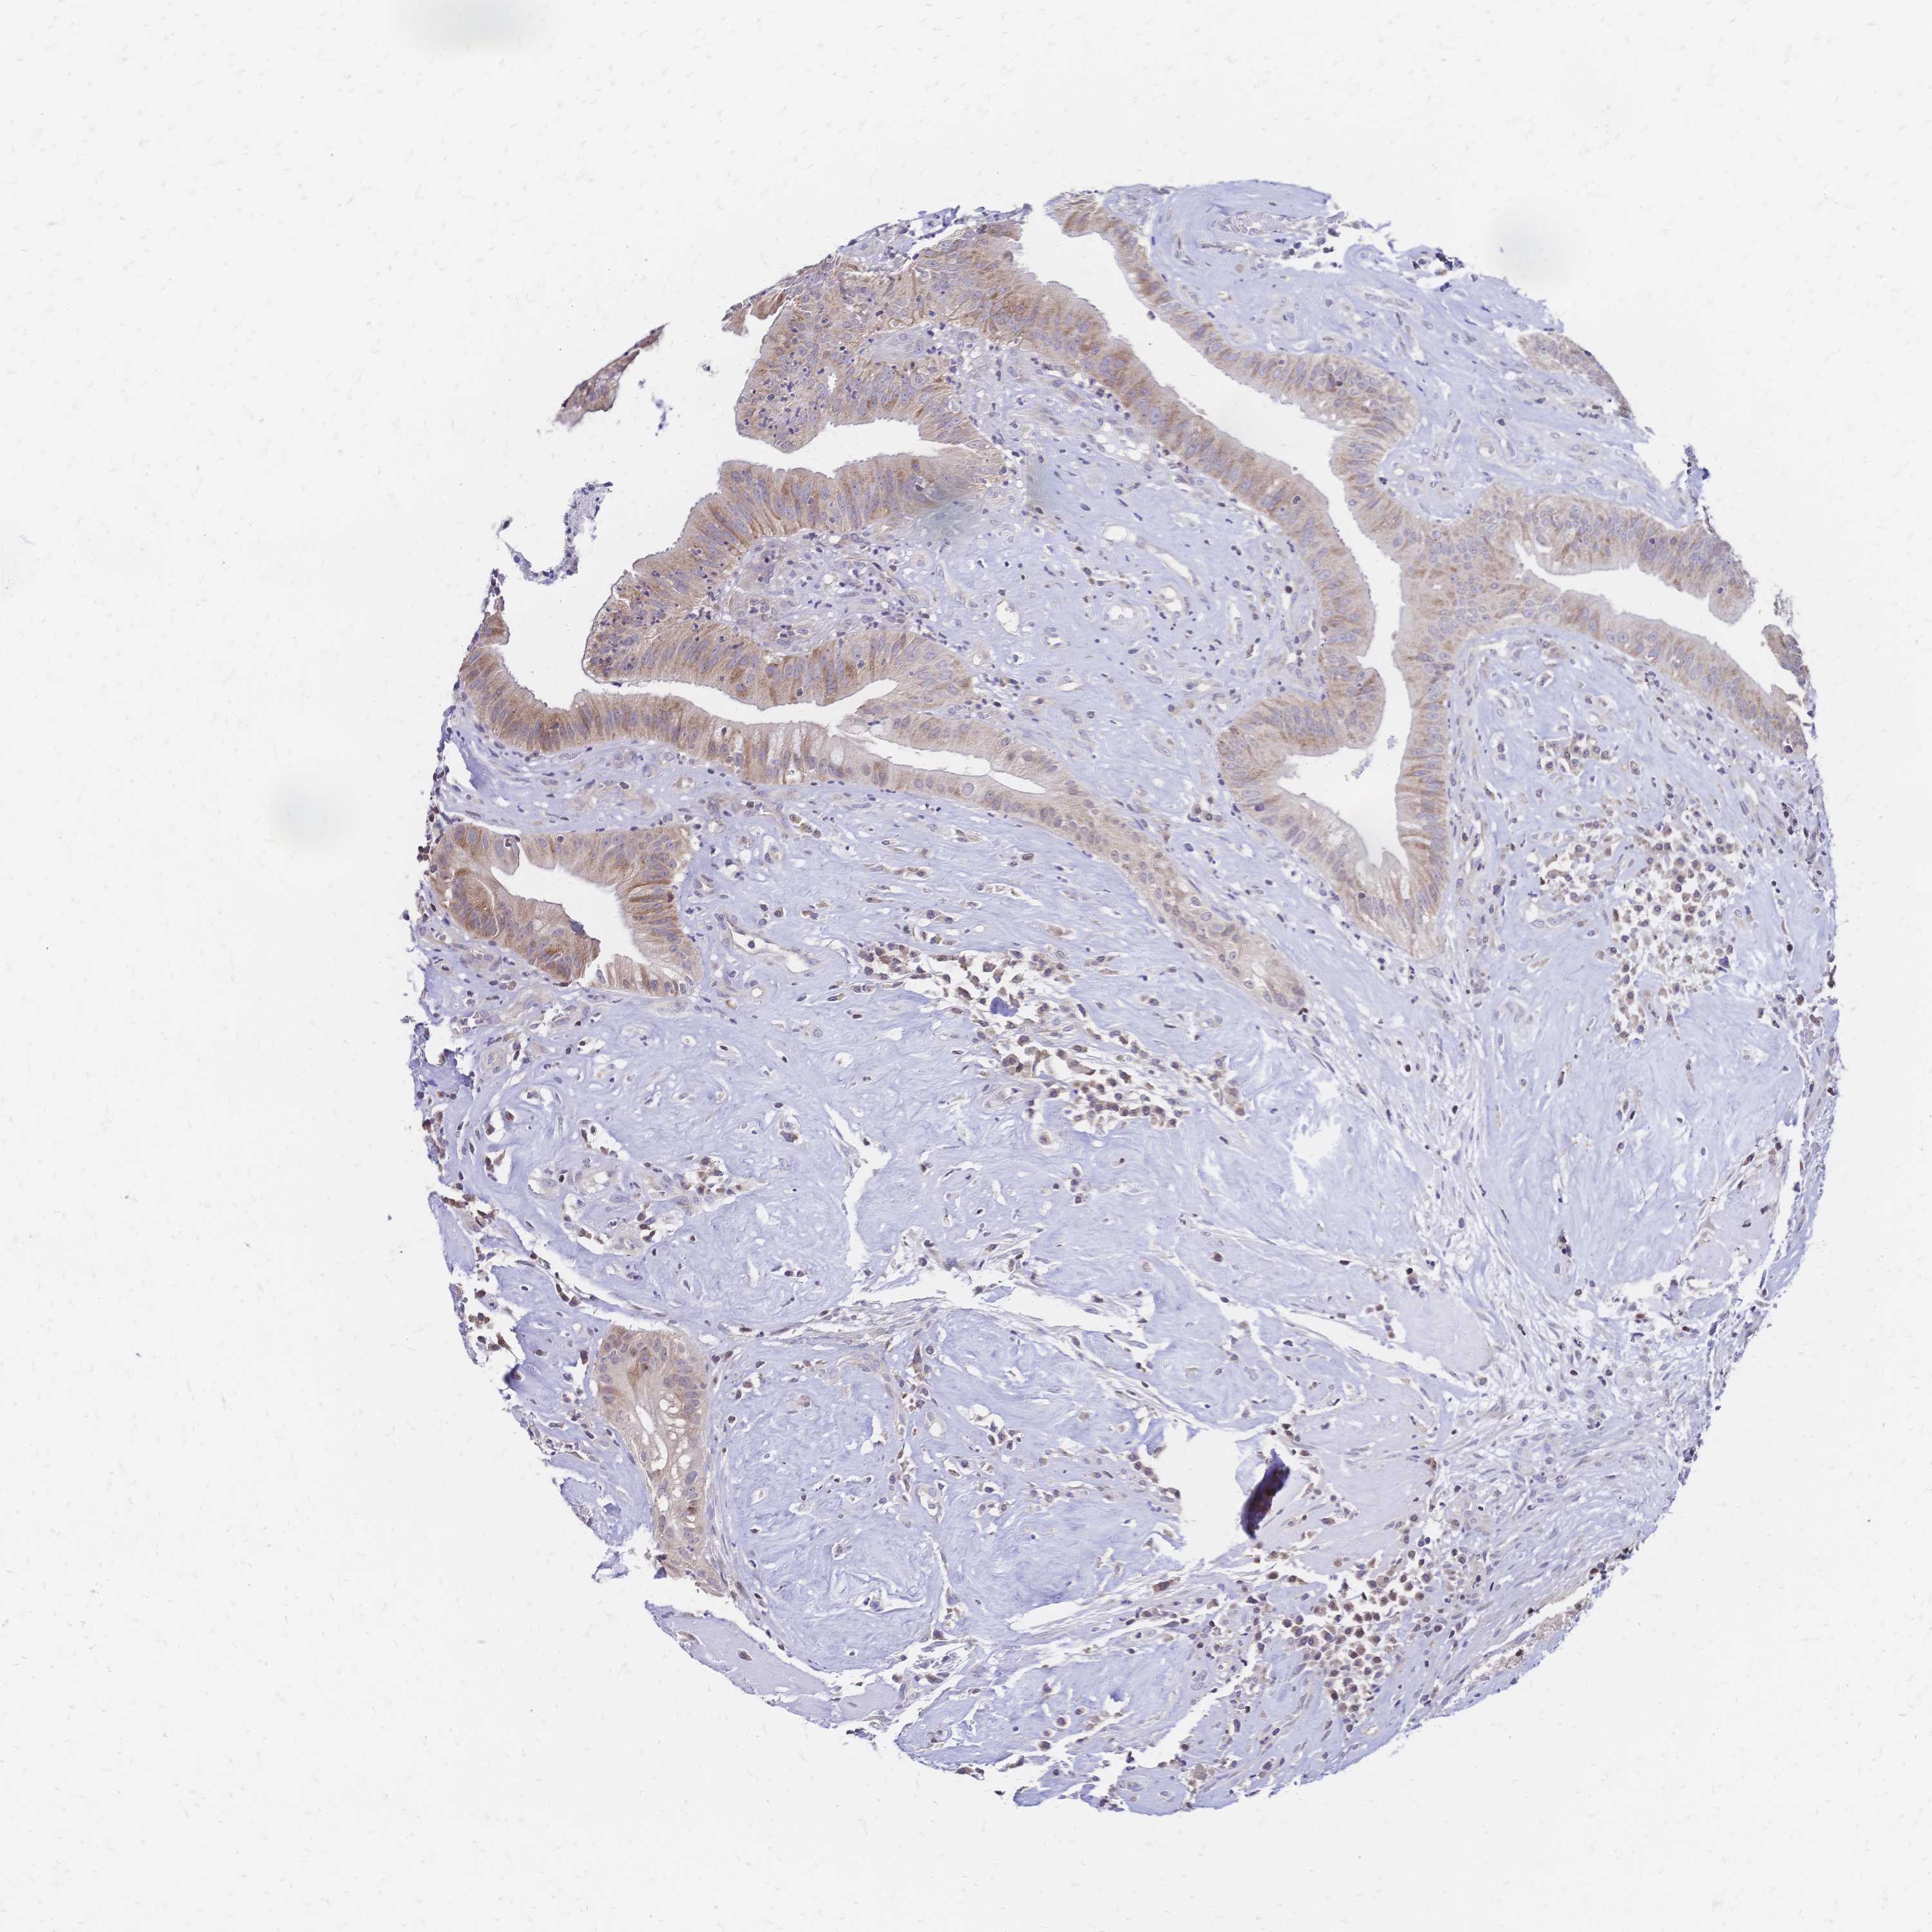

HEAD AND NECK CANCER - Protein expressioni

A mouse-over function shows sample information and annotation data. Click on an image to view it in a full screen mode. Samples can be filtered based on level of antibody staining by selecting one or several of the following categories: high, medium, low and not detected. The assay and annotation is described here.

Antibody stainingi

Antibody staining in the annotated cell types in the current human tissue is reported as not detected, low, medium, or high, based on conventional immunohistochemistry profiling in selected tissues. This score is based on the combination of the staining intensity and fraction of stained cells.

Each image is clickable and will lead to virtual microscopy that enables deeper exploration of all samples and also displays staining intensity scores, fraction scores and subcellular localization as well as patient and tissue information for each sample.

Antibody HPA048677

Antibody HPA056480

Antibody CAB011574

Staining

High

Medium

Low

Not detected

Intensity

Strong

Moderate

Weak

Negative

Quantity

>75%

75%-25%

<25%

None

Location

Nuclear

Cytoplasmic/membranous

Cytoplasmic/membranous,nuclear

Adenocarcinoma, NOS

Squamous cell carcinoma, NOS

Squamous cell carcinoma, metastatic, NOS

Adenoma, NOS